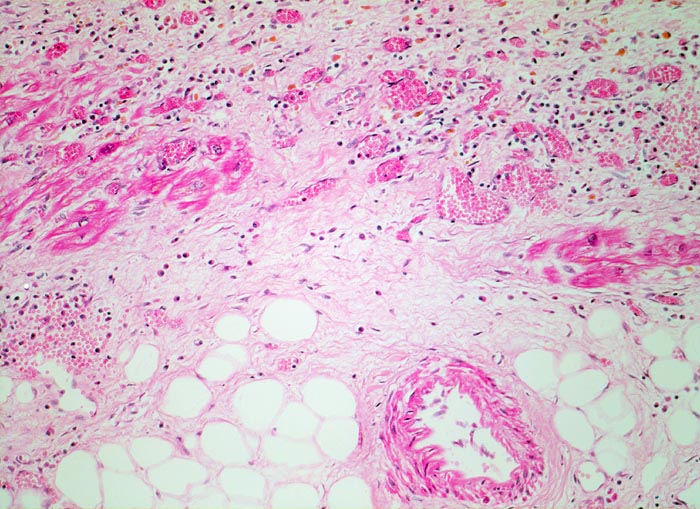

PathoPic – image database / PathoPic ID 4818 - subakuter Myokardinfarkt

subakuter Myokardinfarkt

Das Granulationsgewebe besteht aus lockerem Bindegewebe, Kapillaren und gemischtem Entzündungsinfiltrat. Die hämosiderinhaltigen Makrophagen sind an ihrer gelben Farbe erkennbar. Im Granulationsgewebe eingeschlossen einzelne vitale Myokardzellen.

Ausgedehnter subakuter Myokardinfarkt von Hinterwand und Septum. Im Infarktrandbereich perakute Myokardnekrosen.

Narbengewebe kann ebenfalls vaskularisiert sein. Für die Diagnose eines subakuten Infarktes muss das Granulationsgewebe auch Entzündungszellen enthalten.